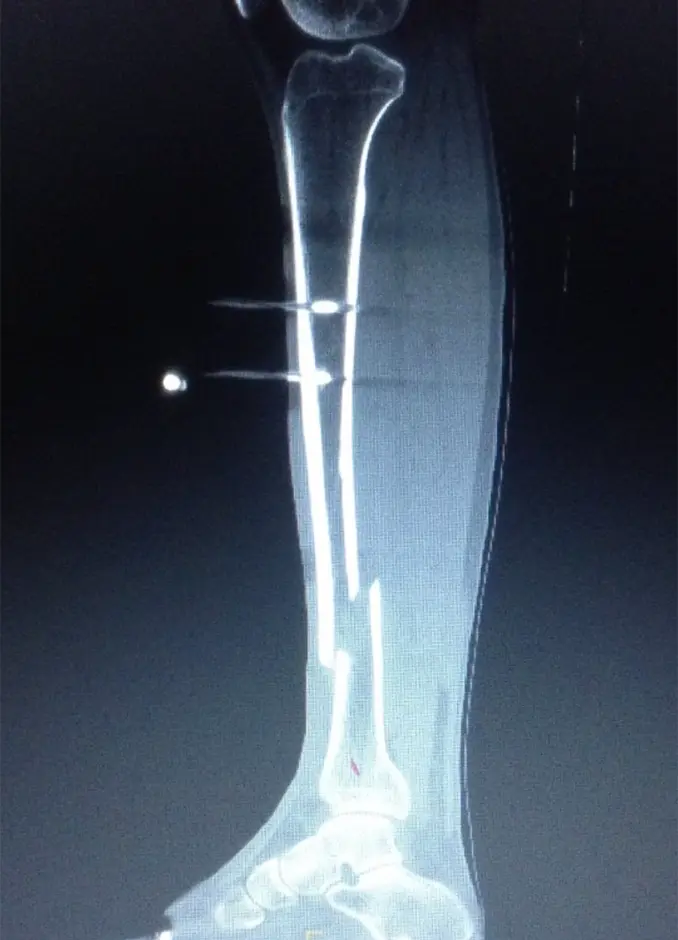

画像所見

初診時のX線にて脛骨遠位骨幹部、腓骨近位部、それぞれにらせん骨折(Müller AO分類 42-A1)を認めた。

(図1)単純レントゲン像